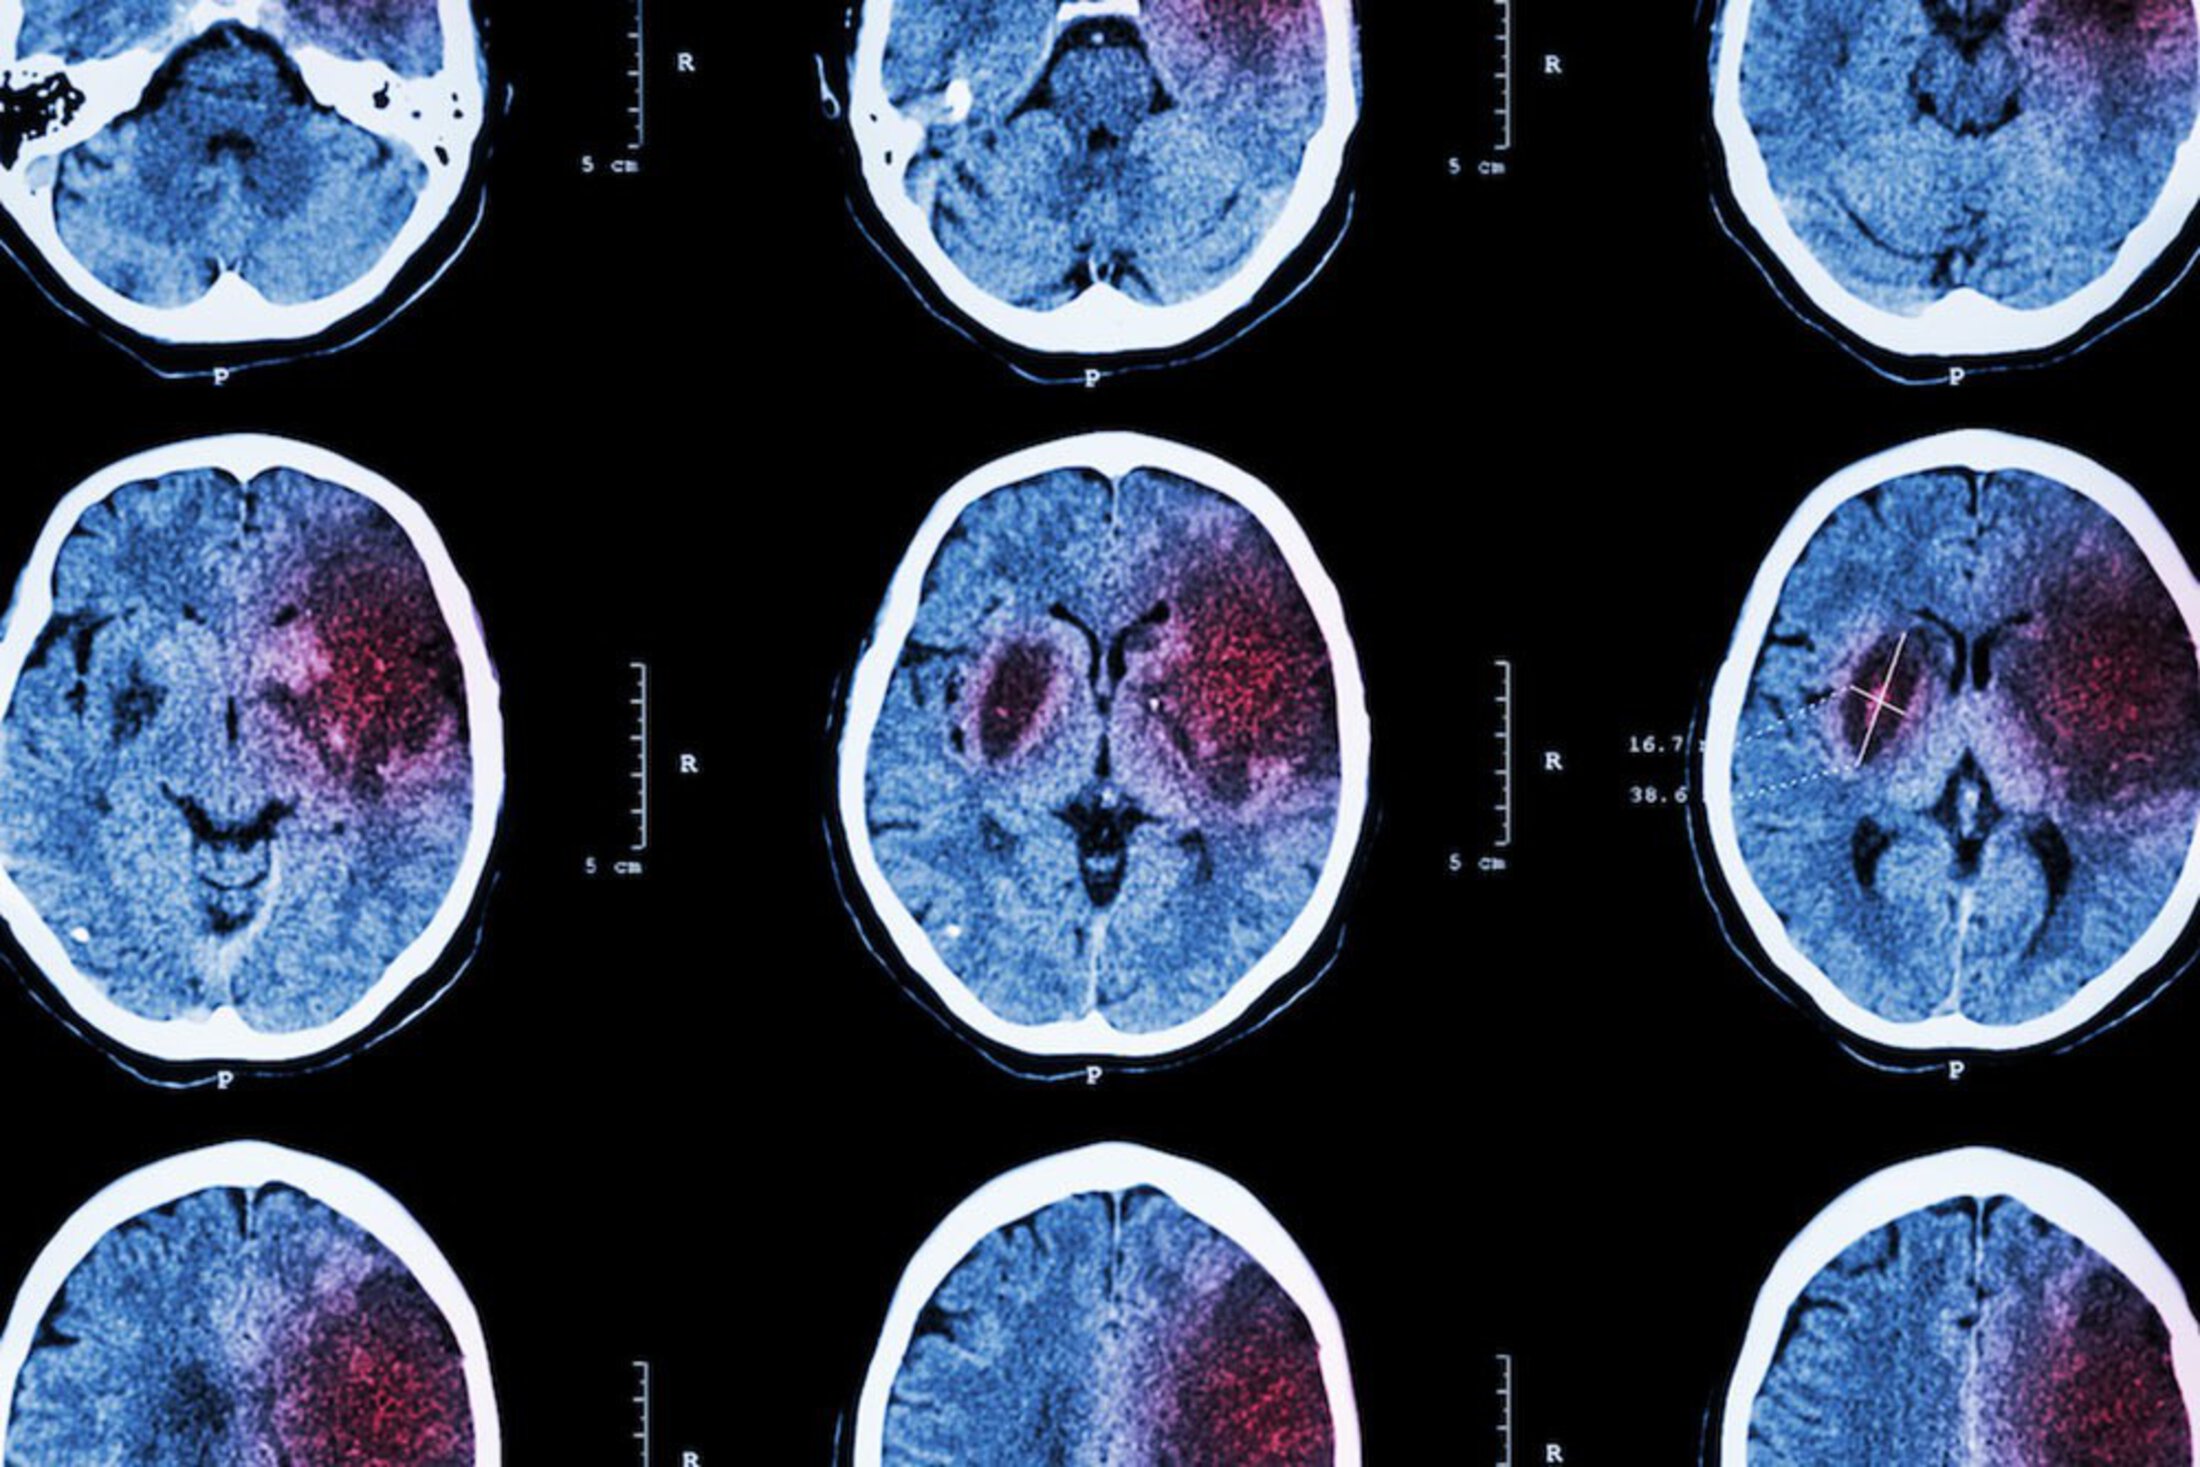

There is plenty to study, said Jauch, as some 800,000 people across the U.S. suffer strokes each year.  South Carolina is part of the “stroke belt,” so named because the incidence of stroke is so much higher than the rest of the country.  South Carolina has the sixth-highest rate of stroke deaths among the states, according to the Centers for Disease Control and Prevention.  Strokes caused 16,484 hospitalizations in the state in 2016, and 39 percent of those hospitalized were less than 65 years old, according to the South Carolina Department of Health and Environmental Control.